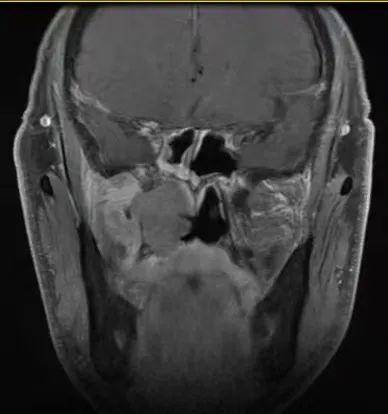

病例1:患者男,56岁,因反复鼻出血入院,入院CT、MRI示肿瘤侵犯右侧翼腭窝、颞下窝、翼突根及翼内外板。入院诊断:侧颅底恶性肿瘤。肿瘤范围大,难度大,风险高。

CT、MRI示肿瘤侵犯右侧翼腭窝、颞下窝、翼突根及翼内外板